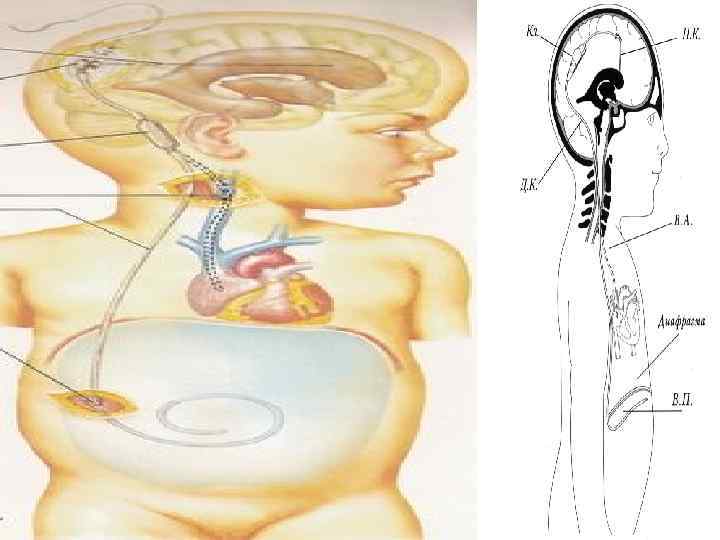

Вентрикулоперитонеальное шунтирование 99

100

101